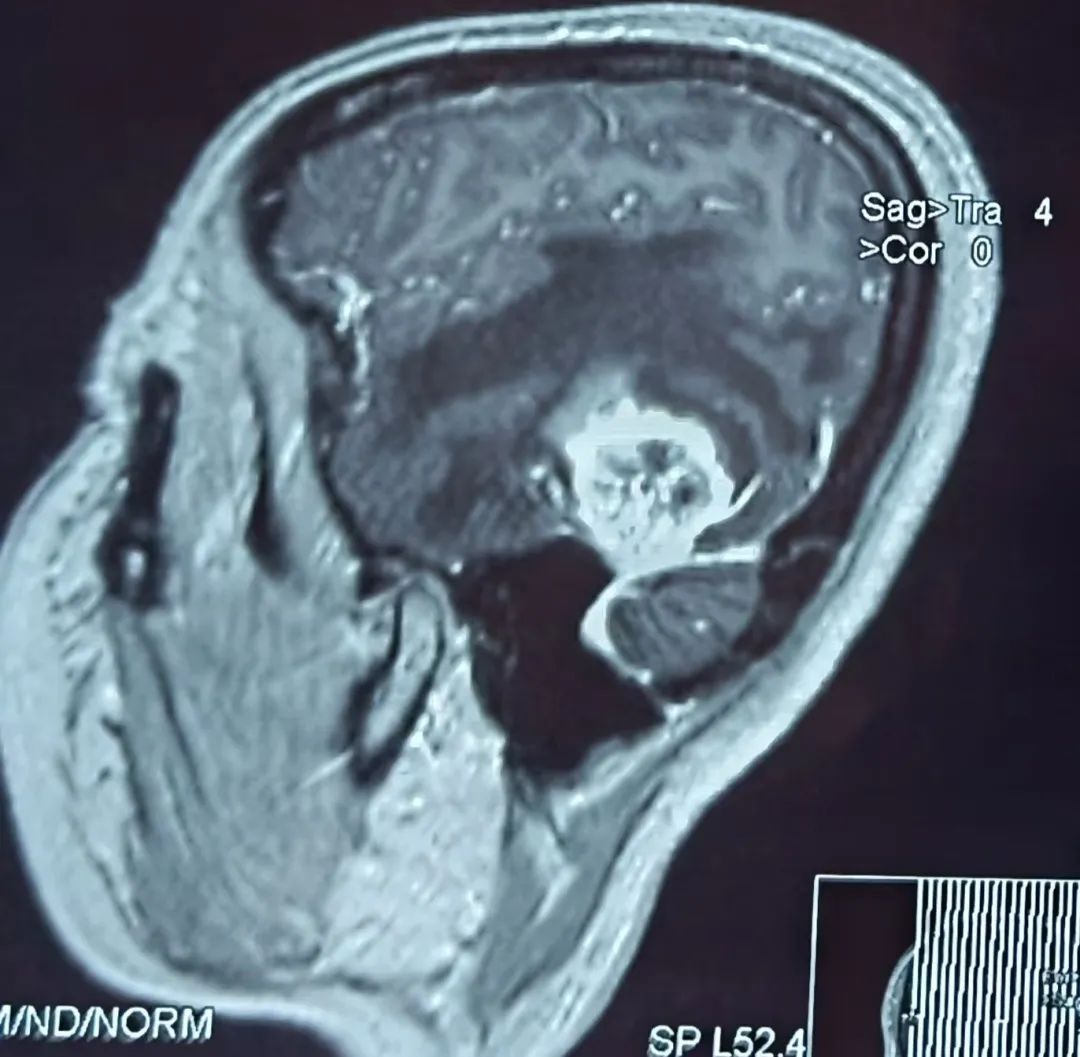

患者43岁,肾肿瘤术后一个半月开始出现头痛难忍,伴有恶心、呕吐、言语不流利,每天靠止痛药缓解头痛,到医院行头部核磁检查提示左颞叶占位,考虑脑转移瘤可能性大。为进一步诊治,在朋友的介绍推荐下,患者来到我院神经外科找到桑文渊主任。桑主任详细询问病史,仔细阅片后,初步诊断患者为脑转移瘤。

患者术前核磁影像

患者入院后经积极术前准备,在麻醉科手术室的积极配合下,桑主任带领神经外科团队尽快为患者实施了左颞开颅肿瘤切除术,由于肿瘤位置较低较深,基底部位于颅底硬膜,部分与小脑幕紧密粘连,且肿瘤质地较韧,血运丰富,所以需要在显微镜下先离断肿瘤基底部血运,才能减少术中出血。